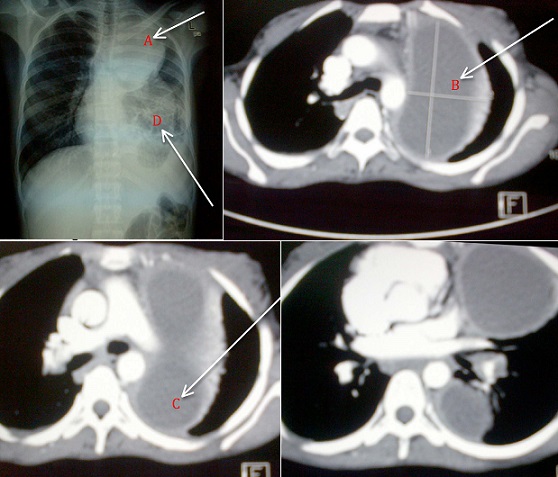

A 32 years-old female, HIV positive who defaulted using Atripla for over a period of one year with current CD4 of 86/µL was referred to a tertiary hospital with chest x-ray showing a lesion suspicious of a lung tumour. She had presented at local hospital three (3) months earlier with non-productive cough, associated with left sided stabbing chest pains and fevers, and treated as a case of community acquired pneumonia. The cough and fevers subsided. Past medical history is remarkable for Pulmonary Tuberculosis in 2004.The patienthas been afebrile throughout her six weeks hospital stay. General examination revealed no respiratory distress, mild pallor and moderate finger clubbing with temperature of 36.70C .Other vitals were within the normal range. Respiratory rate of 19breaths/minute, decreased air entry in the left lower zone posteriorly, left basal coarse crepitations, left upper zone dullness on percussion with bronchial breath sounds. The rest of systemic examination was not remarkable. Full blood count showed normal WBC=6.12K/ul and Neutrophil=4.9K/ul, moderate anemia with Hb=7.4g/dl, MCV=70.1fl and Platelet=283X 109/l. Pus results did not reveal any organisms on culture; Ziehl-Nelson for AFB was negative. Cytology results showed acute and chronic inflammatory cells, with no evidence of malignancy. Computerized tomography of the chest revealed multiple left lung abscesses, Bronchiectasis and fibrosed left middle hemithorax. In view of multiple lung abscesses complicated with bronchiectasis, the cardiothoracic surgeon has planned an elective surgical intervention to drain the abscesses and a pneumonectomy.